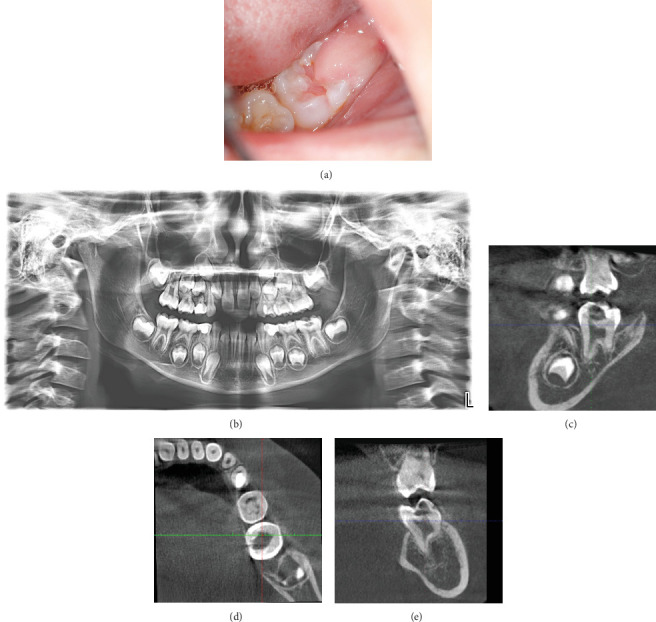

Intracoronal resorption (IR) is a condition characterized by the presence of lesions in the dentin of unerupted or erupting teeth, usually located just below the enamel-dentin junction in the occlusal part of the crown. This article presents two cases of IR-one with and one without pulp involvement. In both cases, the teeth were asymptomatic, and the lesions were discovered during routine checkups. The first case presents pre-eruptive IR with pulp involvement in an immature mandibular molar. To preserve the vitality of the growth zone and complete root development, vital pulp therapy was performed through total coronal pulpotomy and application of Biodentine. The second case is also of a mandibular molar with incomplete root development, but although it initially resembled invasive cervical resorption, treatment revealed that the granulation tissue was surrounded by intact enamel and did not affect the pulp or root of the tooth. No carious lesion was found. The tooth was conventionally restored with a composite filling.